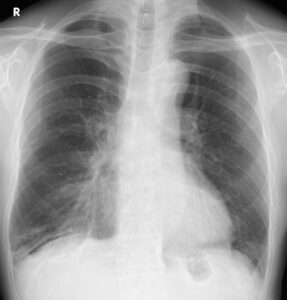

70歳台の男性。気管支喘息のため吸入薬(ICS/LABA/LAMA)を使用していましたが、1週間前から夜間咳嗽が増悪してきたと受診しました。発熱はなく、喀痰も増えていない。下腿浮腫はありませんが、胸部レントゲンでは右下肺野に肺炎?胸水?という感じの微妙な陰影が出現していました。

右下肺野に肺炎? 胸水?